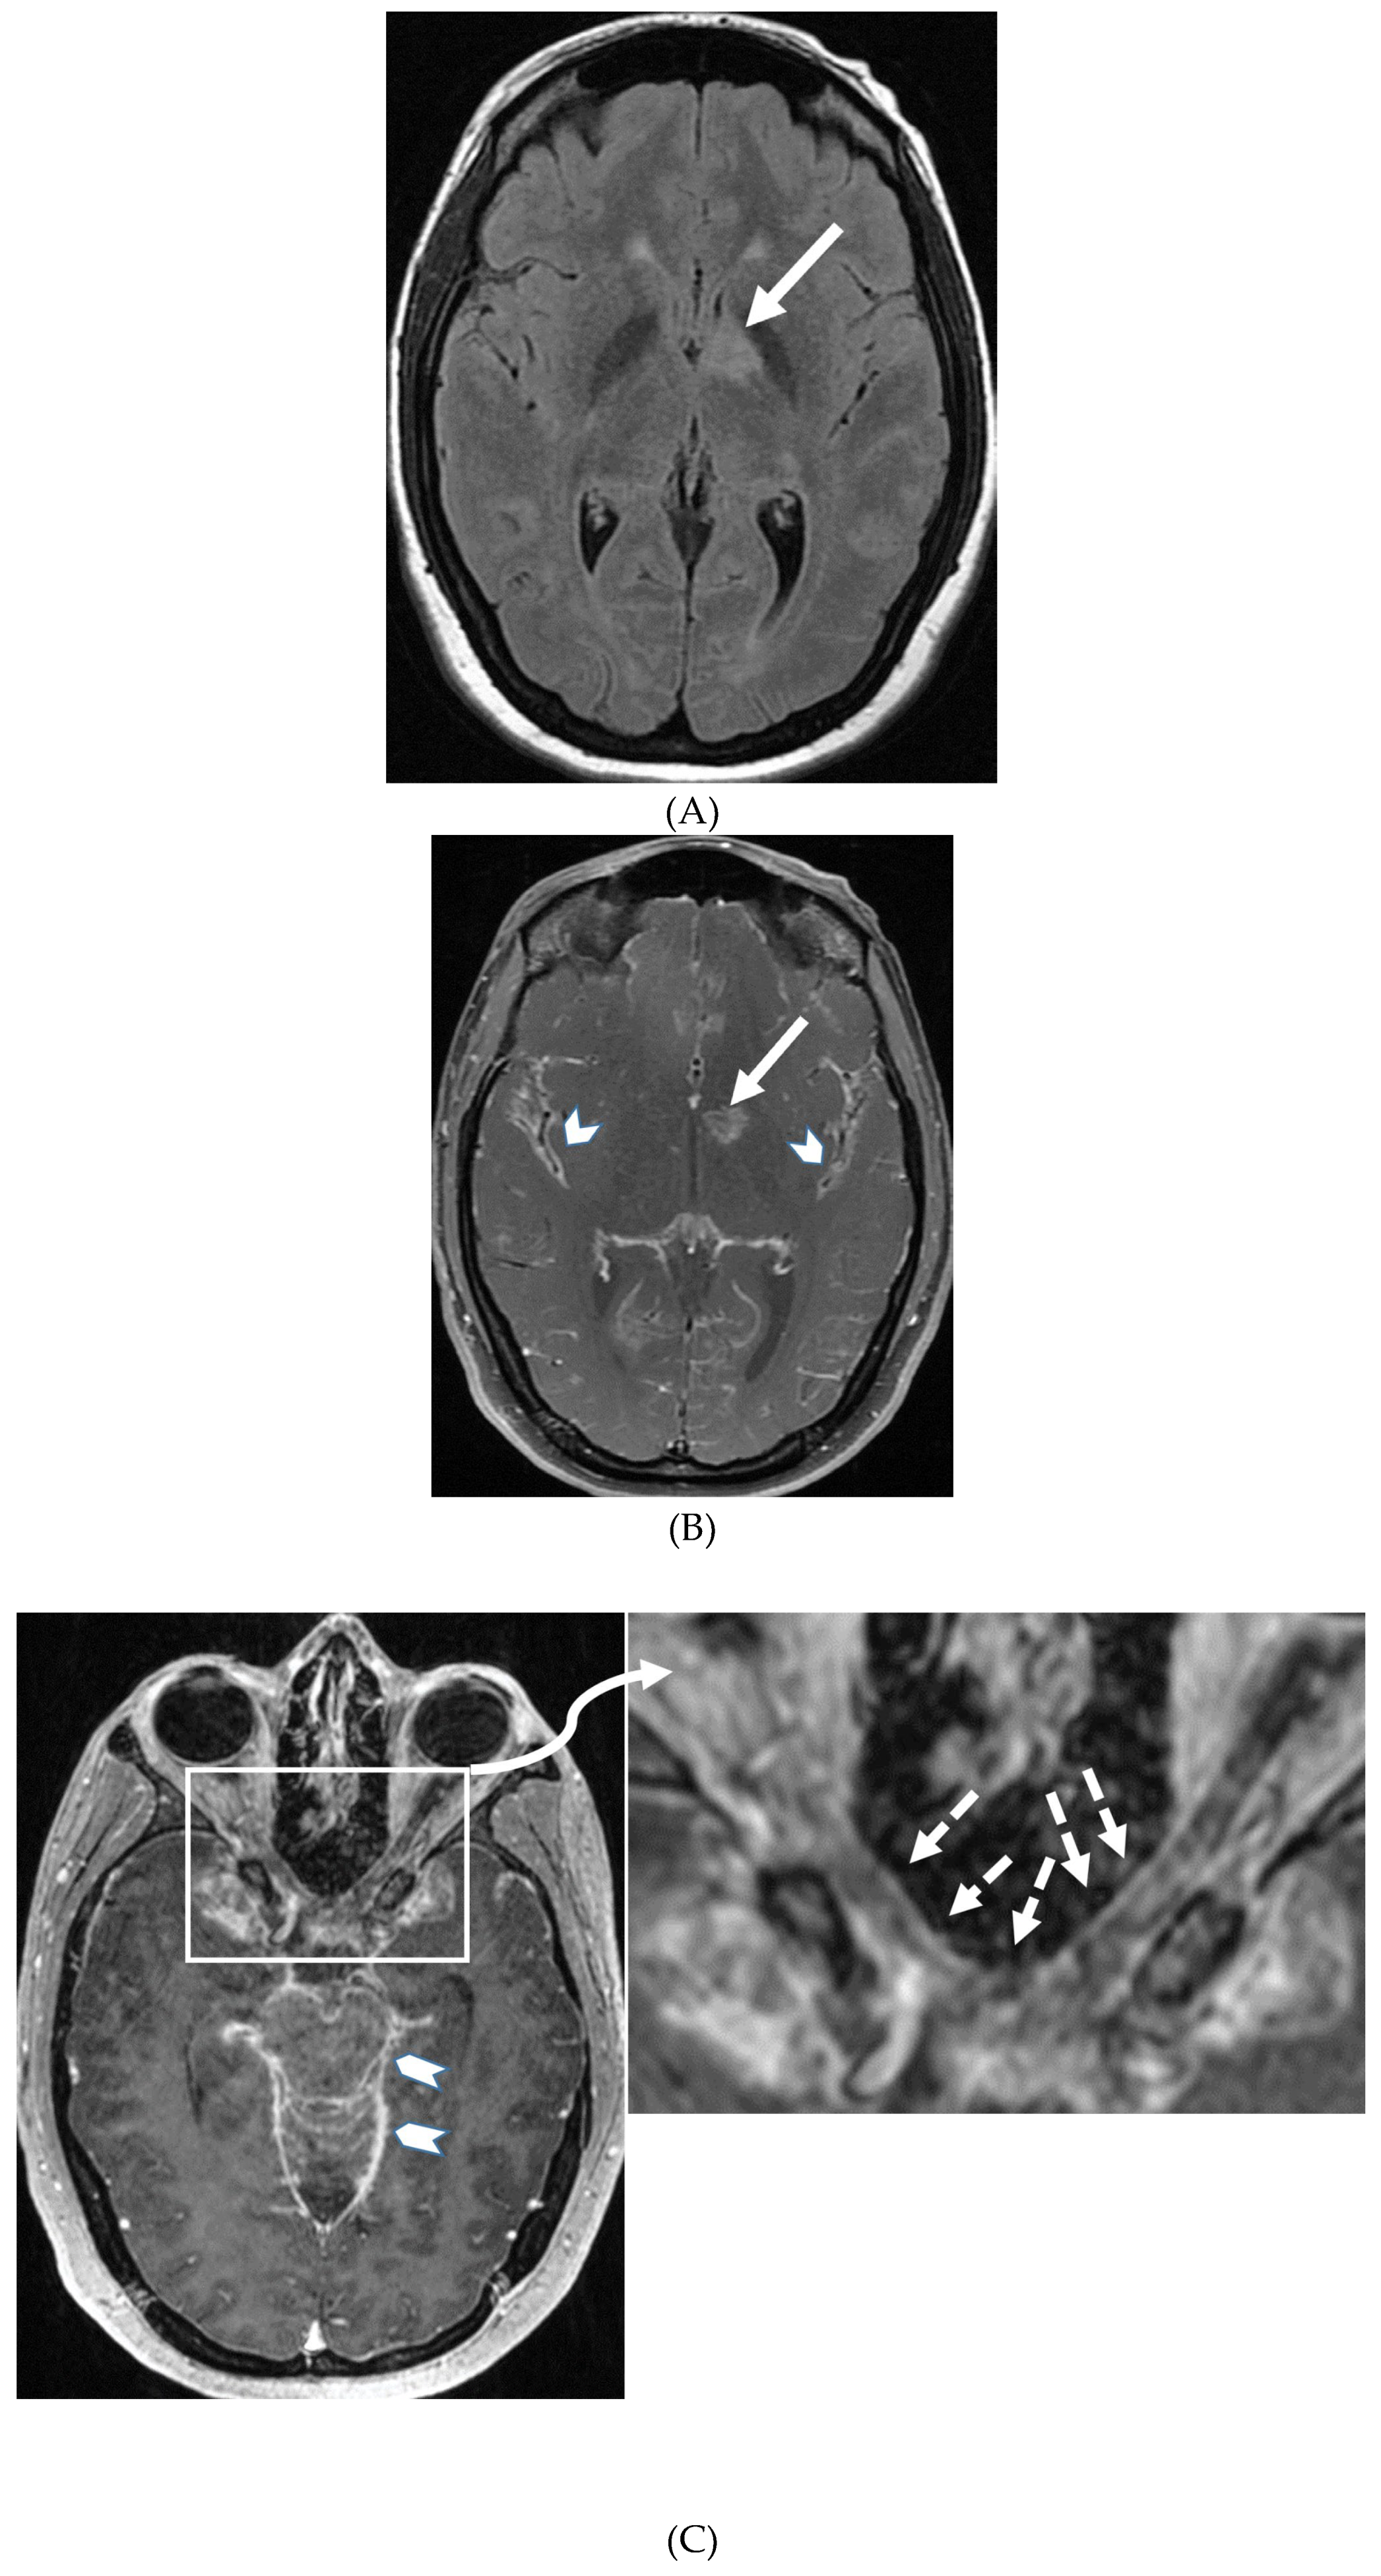

- Horie N, Morikawa M, Nozaki A, Hayashi K, Suyama K, Nagata I. "Brush Sign" on susceptibility-weighted MR imaging indicates the severity of moyamoya disease. AJNR Am J Neuroradiol. 2011 Oct;32(9):1697-702. Epub 2011 Jul 28. PMID: 21799039; PMCID: PMC7965393. [CrossRef]

- Ohta T, Tanaka H, Kuroiwa T. Diffuse leptomeningeal enhancement, "ivy sign," in magnetic resonance images of moyamoya disease in childhood: case report. Neurosurgery. 1995 Nov;37(5):1009-12. PMID: 8559324. [CrossRef]

- Maeda M, Tsuchida C. "Ivy sign" on fluid-attenuated inversion-recovery images in childhood moyamoya disease. AJNR Am J Neuroradiol. 1999 Nov-Dec;20(10):1836-8. PMID: 10588105; PMCID: PMC7657767.

- Liu ZW, Han C, Wang H, Zhang Q, Li SJ, Bao XY, Zhang ZS, Duan L. Clinical characteristics and leptomeningeal collateral status in pediatric and adult patients with ischemic moyamoya disease. CNS Neurosci Ther. 2020 Jan;26(1):14-20. Epub 2019 Apr 13. PMID: 31875482; PMCID: PMC6930821. [CrossRef]